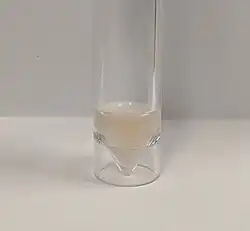

Lumbar puncture

A lumbar puncture is done by positioning the person, usually lying on the side, applying local anesthetic, and inserting a needle into the dural sac (a sac around the spinal cord) to collect cerebrospinal fluid (CSF). When this has been achieved, the "opening pressure" of the CSF is measured using a manometer. The pressure is normally between 6 and 18 cm water (cmH2O);[52] in bacterial meningitis the pressure is usually elevated.[8][48] In cryptococcal meningitis, intracranial pressure is markedly elevated.[53] The initial appearance of the fluid may prove an indication of the nature of the infection: cloudy CSF indicates higher levels of protein, white and red blood cells and/or bacteria, and therefore may suggest bacterial meningitis.[8]